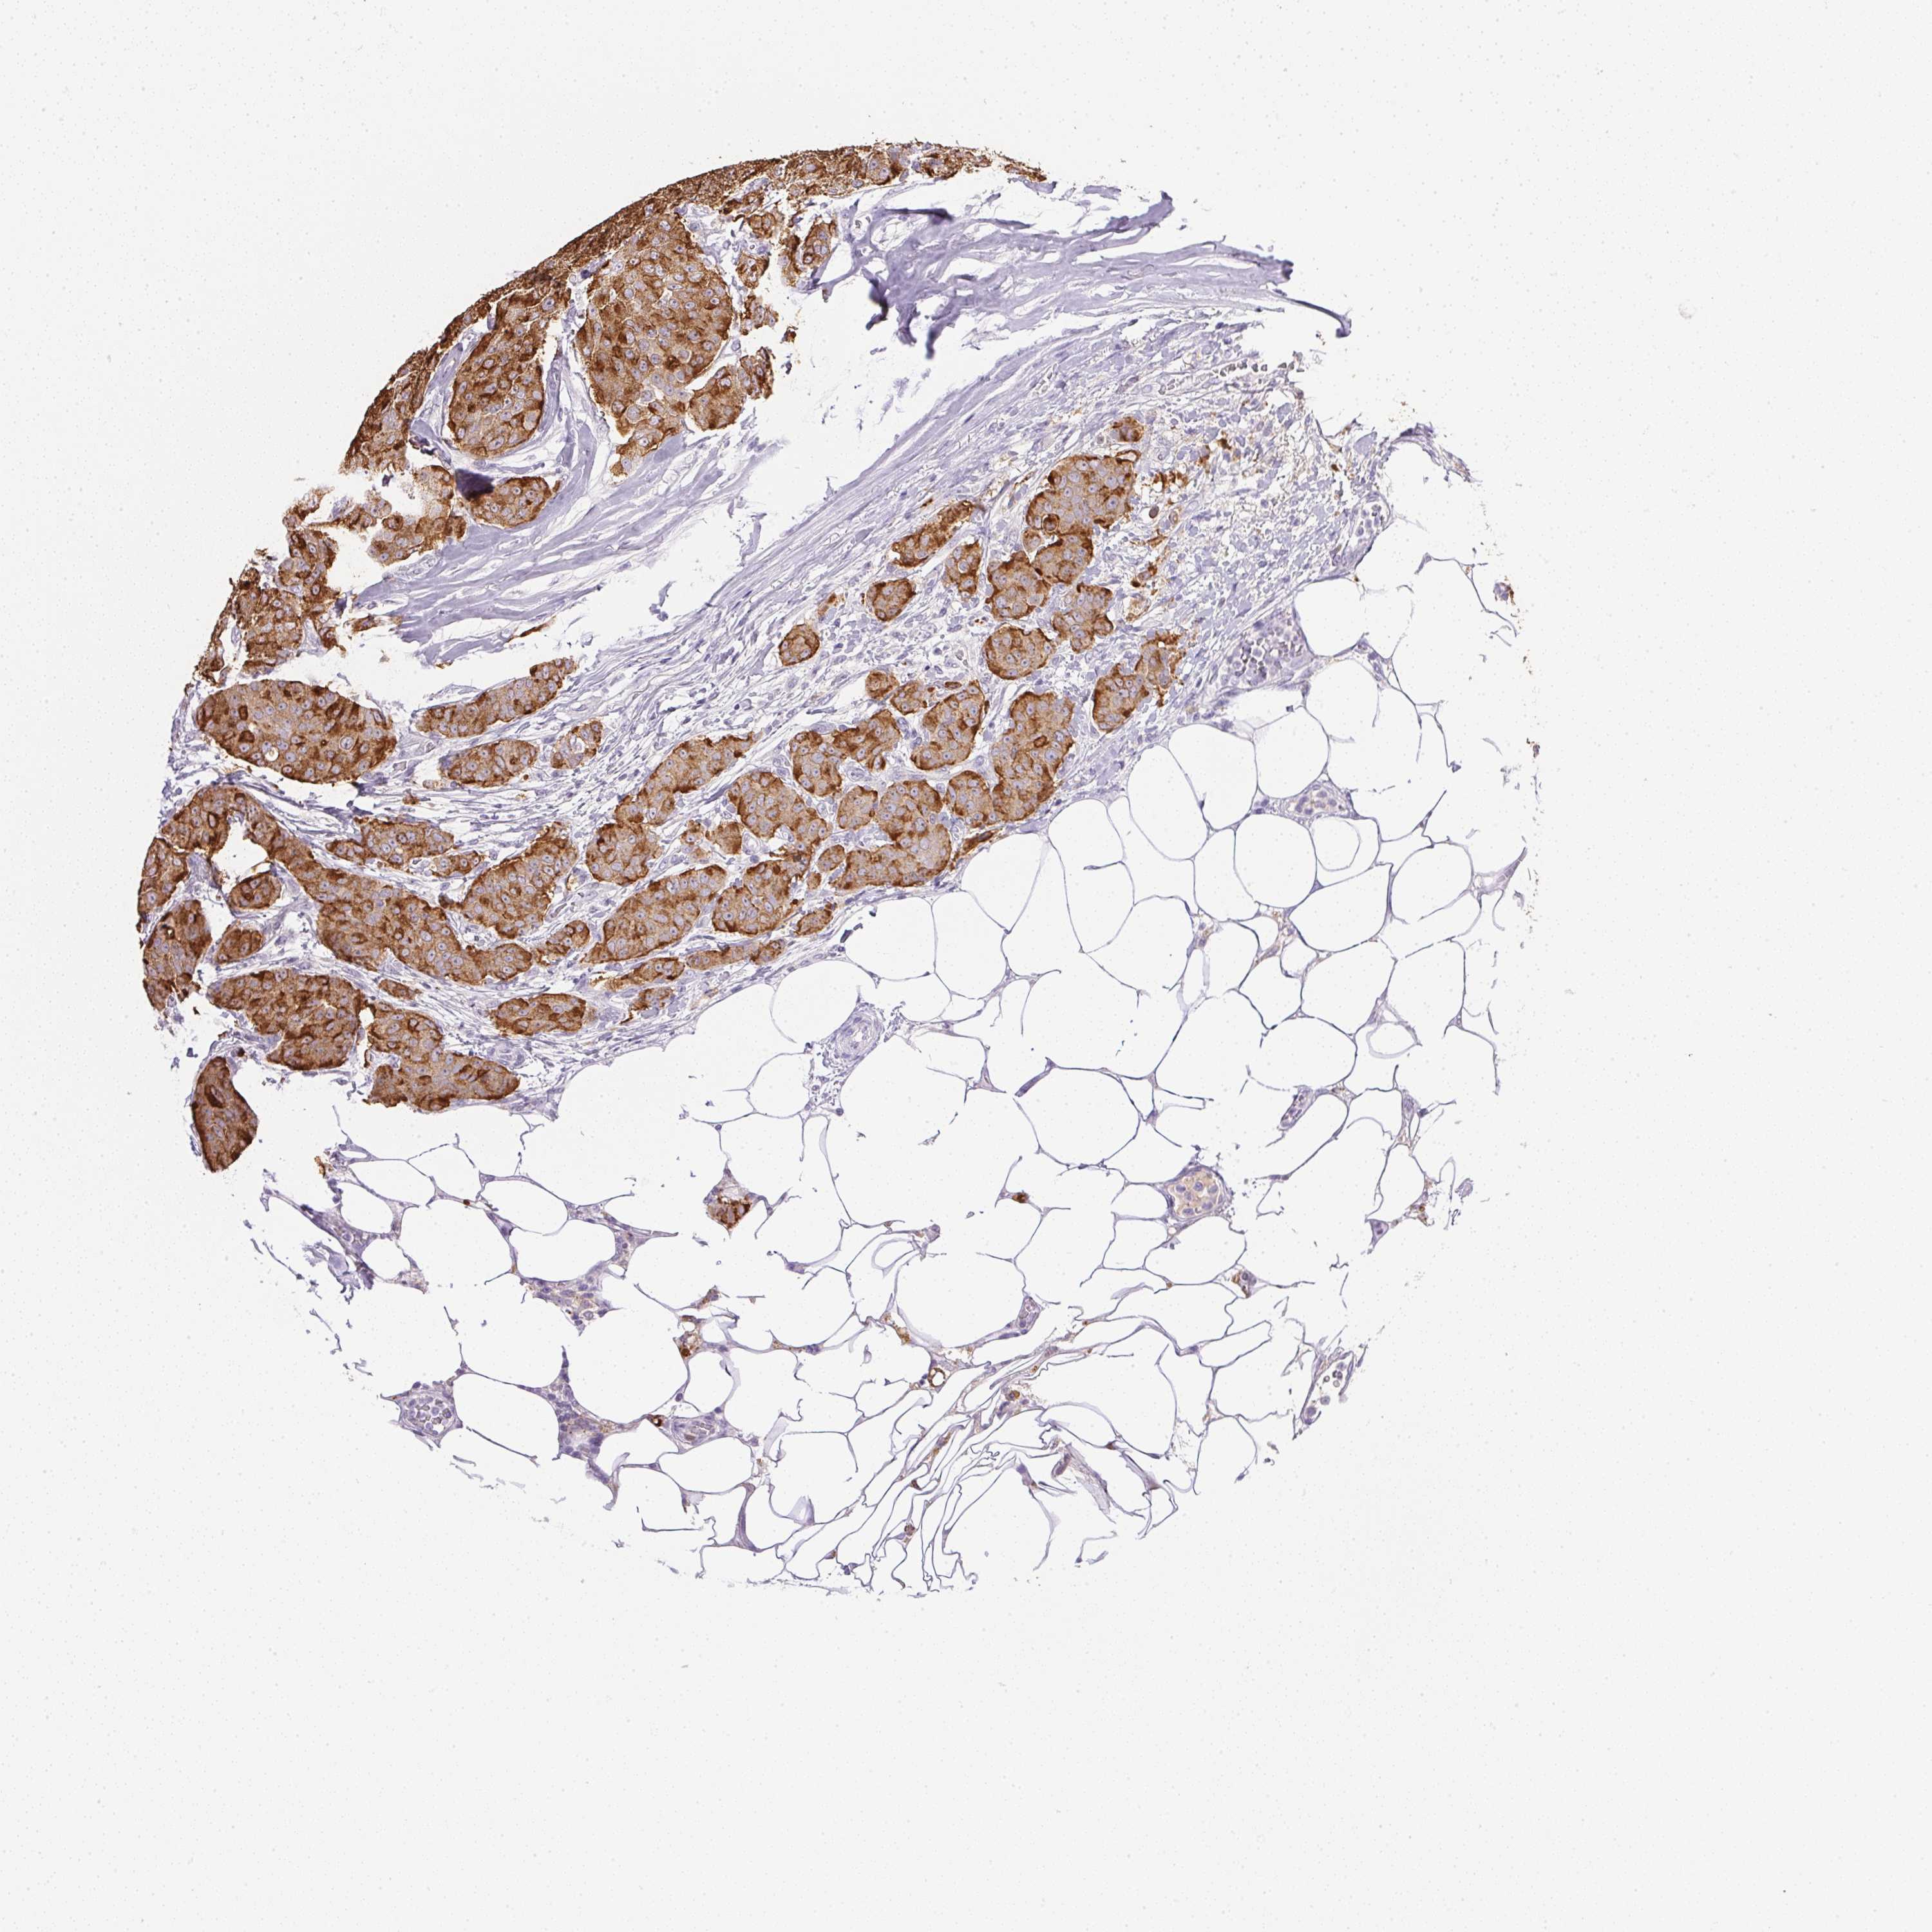

CANCER BREAST CANCER Show tissue menu

BRCA TCGA BRCA VALIDATION PROTEIN EXPRESSION

ANTIBODIES

AND

VALIDATION